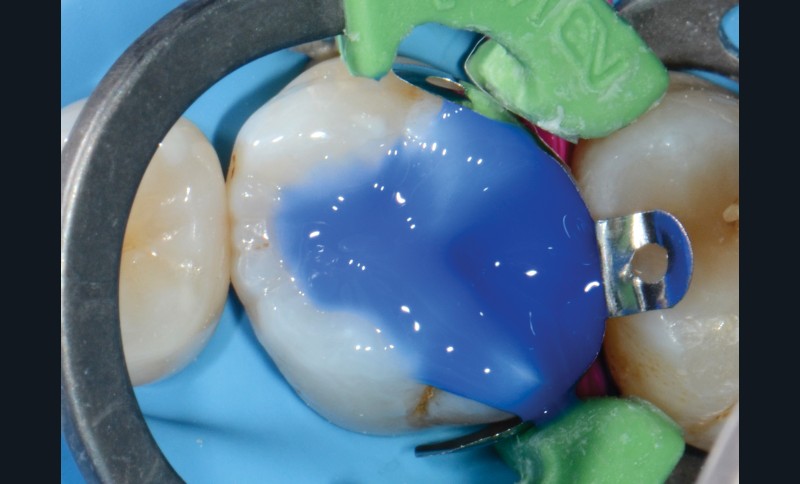

Ce second volet déroule la séquence complète de réalisation d’un composite au travers de deux cas cliniques. Il illustre en particulier la technique de stratification qui débute systématiquement pour les cavités de classe II par la réalisation du mur proximal [2, 3, 4]. Cette première étape permet d’améliorer l’étanchéité et de transformer la préparation occluso-proximale en une cavité de classe I, plus simple à reconstruire. L’utilisation d’une fine couche de flow (0,5 mm), préconisée par certains auteurs [5, 6, 7, 8], est censée optimiser l’étanchéité et l’adaptation. En effet, sa faible viscosité lui confère une bonne mouillabilité tandis que son bas module d’élasticité lui permet d’absorber les contraintes. Nous verrons aussi comment le montage des masses par apports obliques successifs permet de lutter contre la contraction de polymérisation et d’améliorer la photopolymérisation.